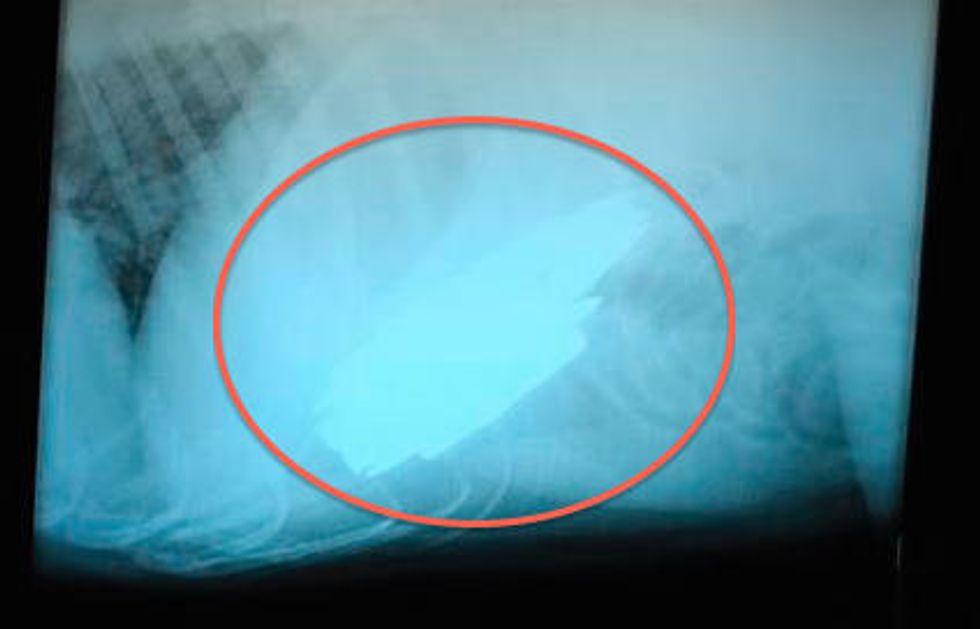

Brassfield took Benno to All Creatures Animal Hospital where Dr. Sarah Sexton took X-rays of the dog's stomach. Sexton said she's seen dogs who have eaten things before – mostly stuffed toys – but added that this one "takes the cake."

The X-ray found that Benno had eaten 23 live rounds of .308 caliber ammunition.

"If you think of the stomach as a balloon, where I made my incision, all the heavy metal went to the bottom," Sexton said. "I had to scoop it all up and bring it up to the location of my incision."

Once she thought she had it all she did another X-ray but discovered there were two more rounds in Benno's esophagus. But the vet had already sewn the dog's incision back up and decided not to remove the other rounds, opting instead to see if he would vomit them up or pass them.